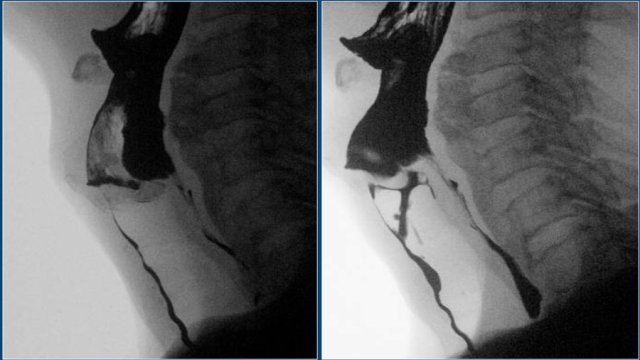

On the left DC views of the pharynx.

Outpounching of the lateral wall of the pharynx is normal and can be quite severe (Dizzy Gillespie).

These are called 'lateral pharyngeal ears'.

Pharyngeal ears

Outpounching of the lateral wall of the pharynx are called 'lateral pharyngeal ears'.

Sometimes patients complain of globus sensation or that small food particles or pills get stuck in their throat, but usually it is an incidental finding.

They can be quite prominent as in Dizzy Gillespie the famous trumpet player.

Two cases of pharyngeal ears.